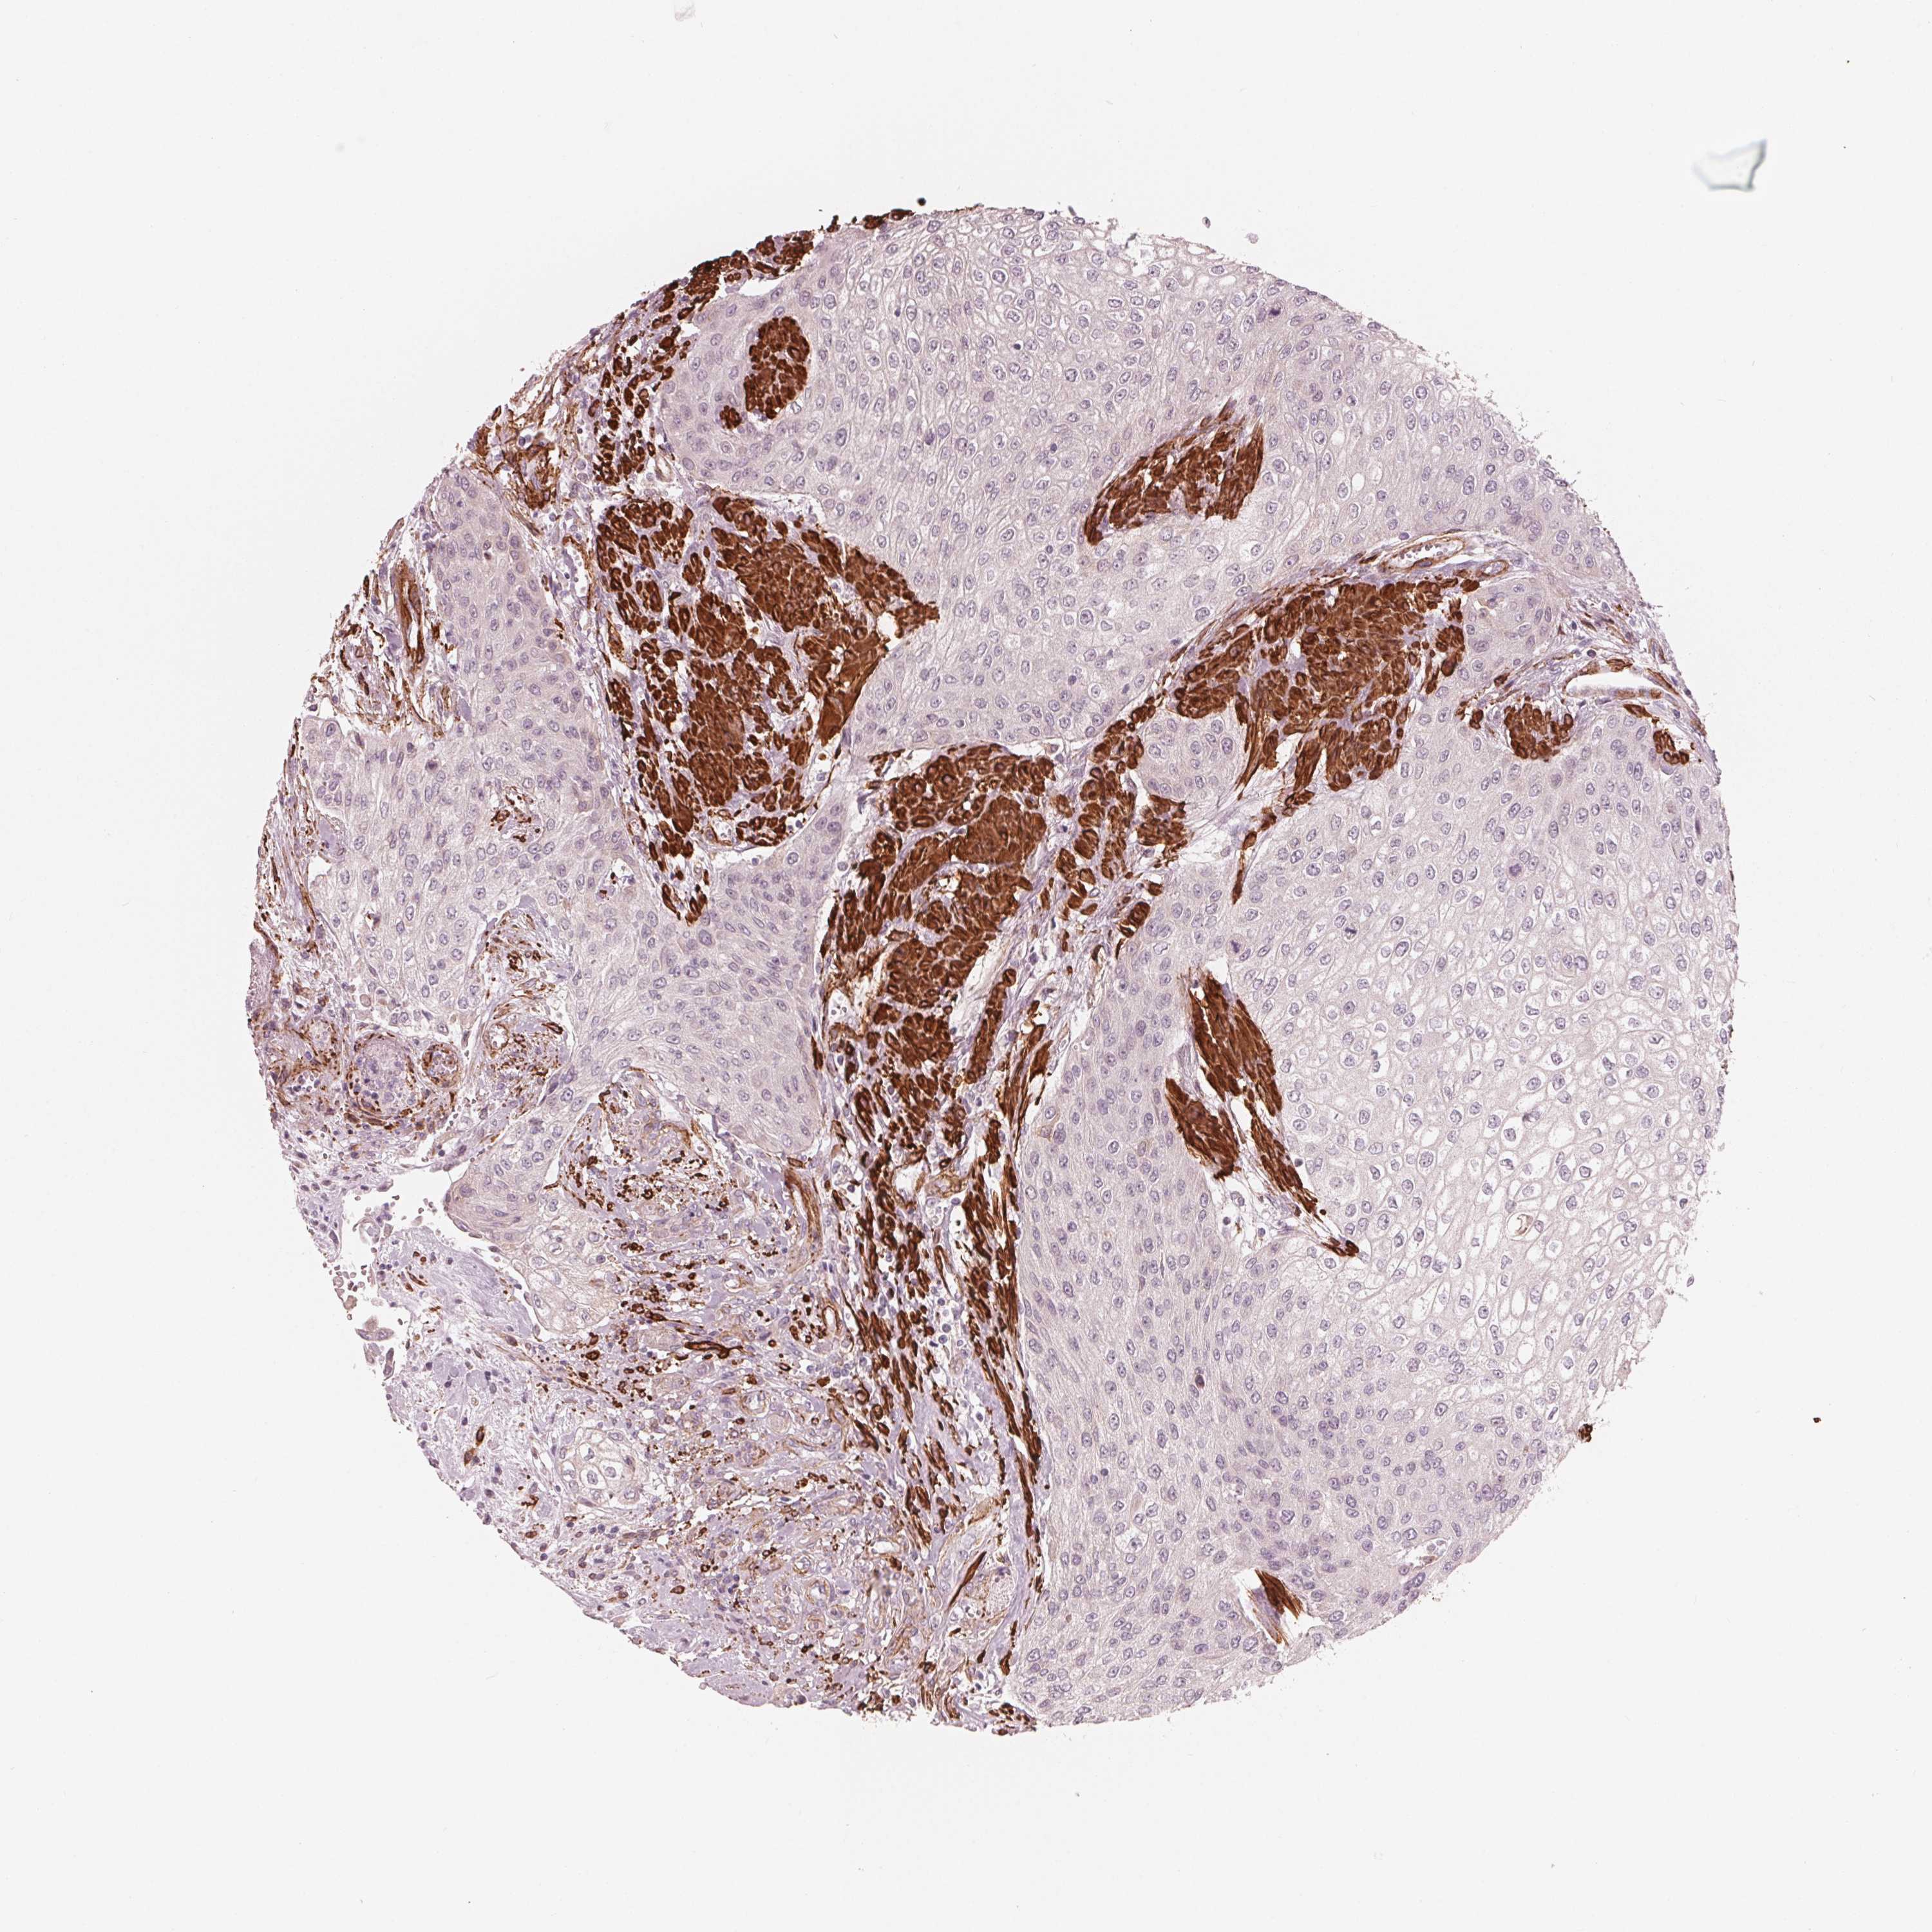

UROTHELIAL CANCER - Protein expressioni

A mouse-over function shows sample information and annotation data. Click on an image to view it in a full screen mode. Samples can be filtered based on level of antibody staining by selecting one or several of the following categories: high, medium, low and not detected. The assay and annotation is described here.

Antibody stainingi

Antibody staining in the annotated cell types in the current human tissue is reported as not detected, low, medium, or high, based on conventional immunohistochemistry profiling in selected tissues. This score is based on the combination of the staining intensity and fraction of stained cells.

Each image is clickable and will lead to virtual microscopy that enables deeper exploration of all samples and also displays staining intensity scores, fraction scores and subcellular localization as well as patient and tissue information for each sample.

Antibody HPA065946

Staining

High

Medium

Low

Not detected

Intensity

Strong

Moderate

Weak

Negative

Quantity

>75%

75%-25%

<25%

None

Location

Nuclear

Cytoplasmic/membranous

Cytoplasmic/membranous,nuclear

Urothelial carcinoma, High grade

Urothelial carcinoma, NOS

Urothelial carcinoma, Low grade